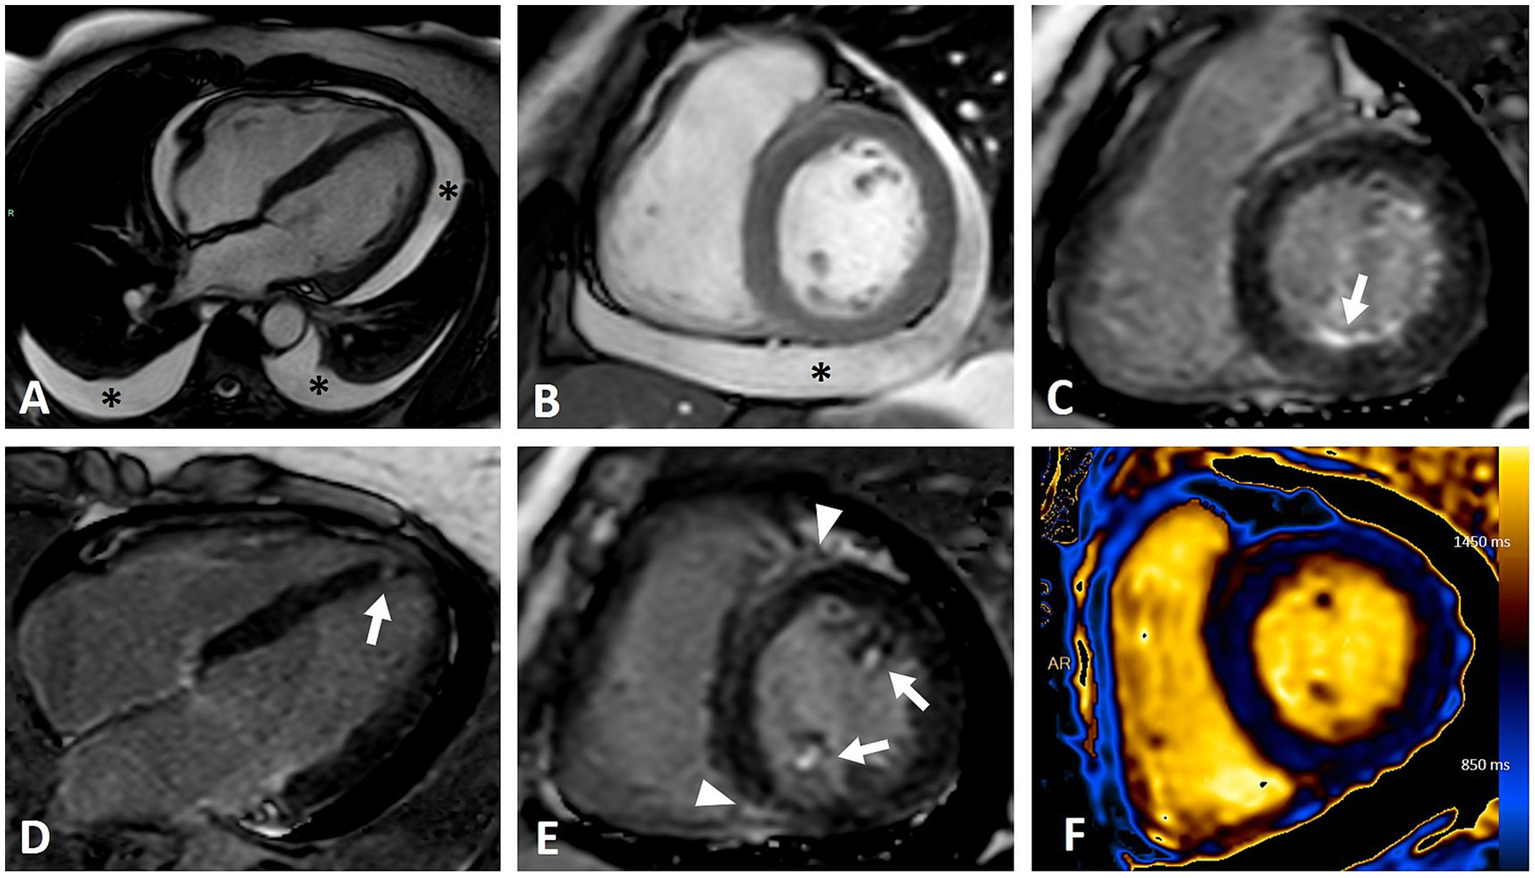

Figure 2

CMR imaging of a female patient with diffuse cutaneous systemic sclerosis and heterogeneous cardiac involvement. (A,B) Moderate pericardial and bilateral pleural effusion (asterisks) in four-chambers (A) and short axis (B) steady-state free precession (SSFP) sequences. (C–E) Inversion recovery sequences demonstrating various patterns of LGE: infero-basal subendocardial (C, arrow), focal septal apical (D, arrow), papillary muscles involvement (E, arrows), insertional (E, arrowhead). (F) T1 mapping showing abnormal elevated values (mean value of 1,100 ms) due to myocardial fibrosis and edema.